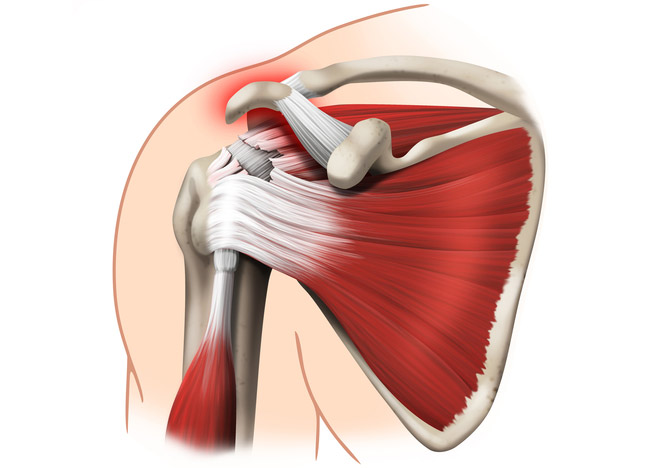

Protocol de investigație prin rezonanță magnetică pentru umăr

Planuri de examinare prin rezonanță magnetică pentru umăr

Pentru identificarea corectă a structurilor anatomice din punct de vedere imagistic, avem nevoie de un protocol corect de investigație prin rezonanță magnetică.